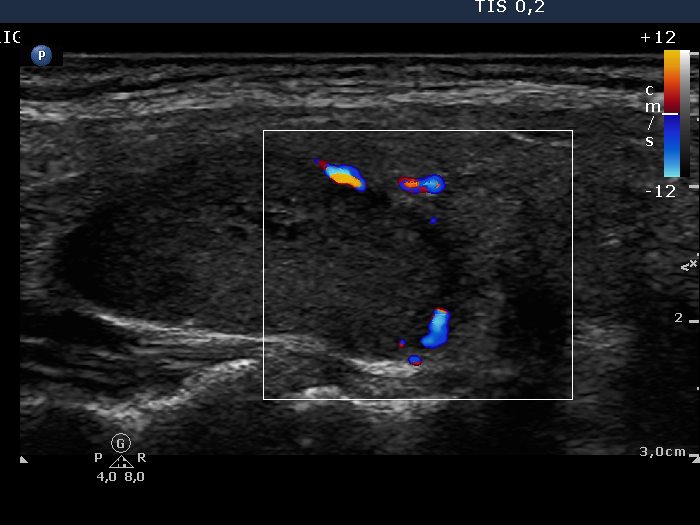

Oxyphilic adenoma - Case 1. (ultrasonographic picture 4)

Right lobe, longitudinal scan, color Doppler mode. Signs of perinodular blood flow.